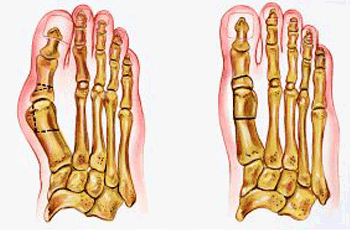

TÉCNICA QUIRURGICA

Haga click para agrandar las imágenes